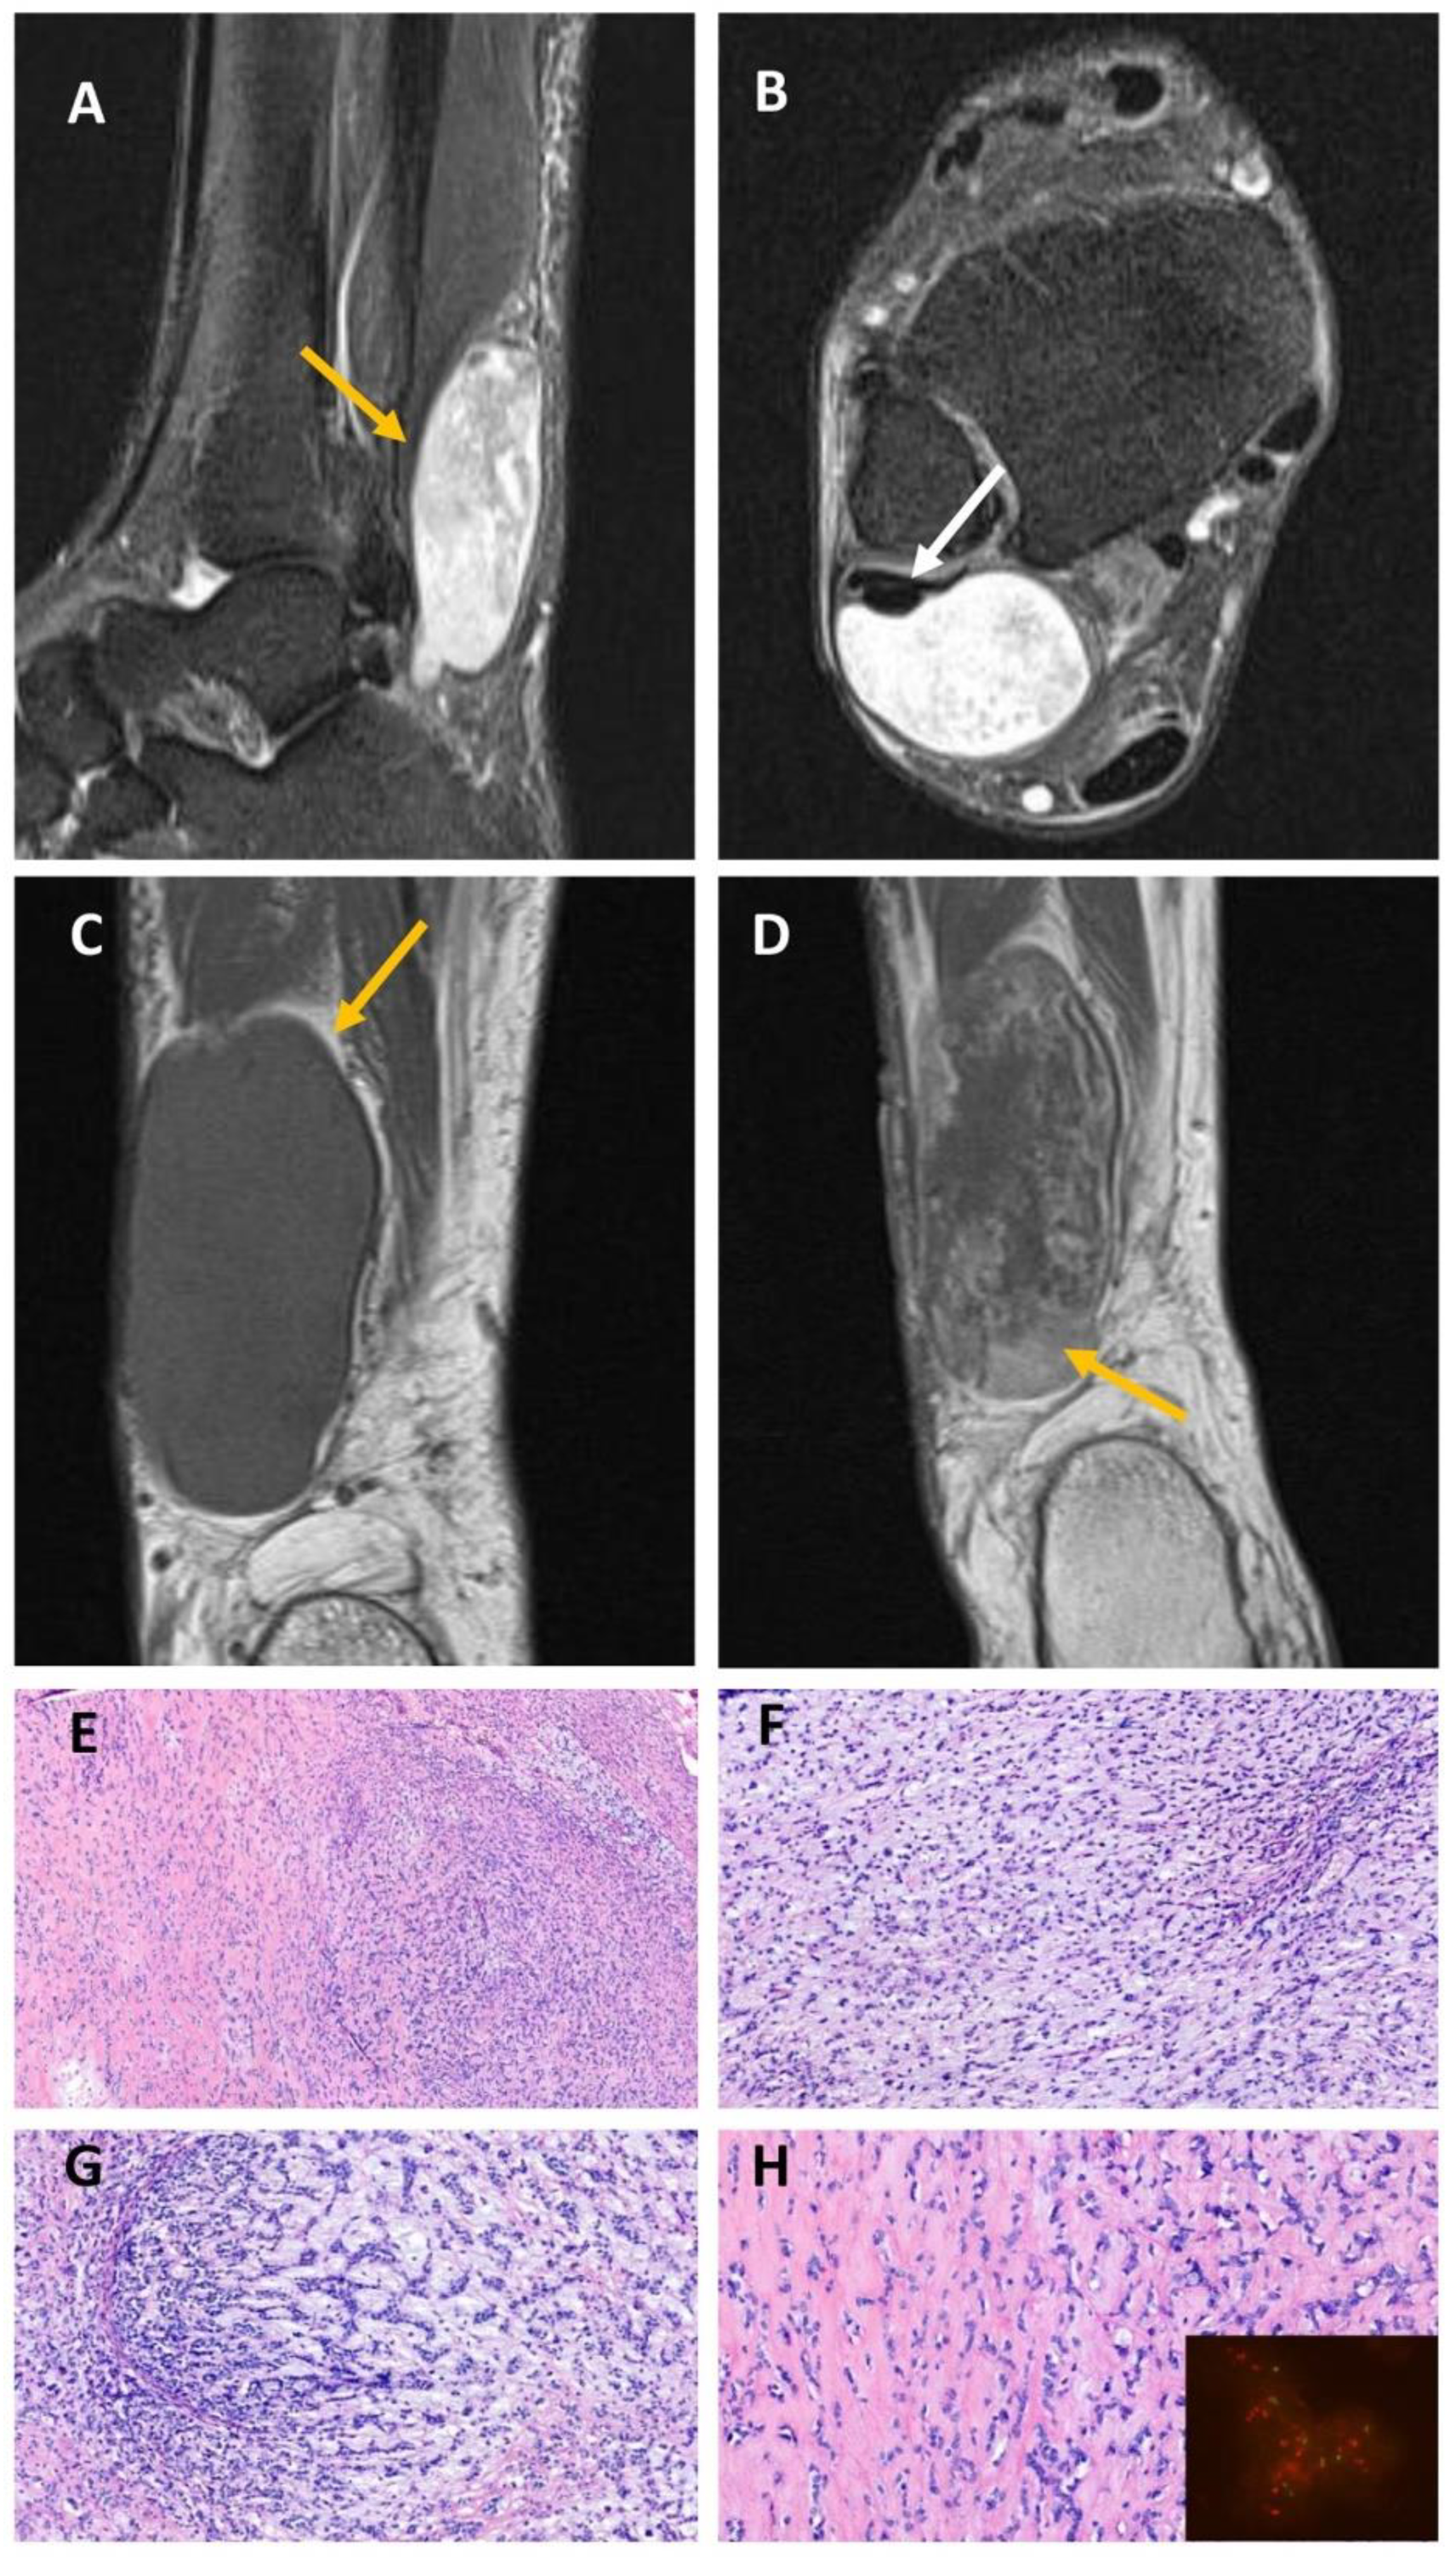

2.3. EWSR1::NFATC2-Rearranged Soft Tissue Sarcoma (Case #4)

| 4 | 69 | m | lower leg (distal fibularis brevis muscle) | 3.2 cm | EWSR1::NFATC2 | positive | positive | gain 22q1.1-13.2 loss 22q1.21-1.23 gain 22q1.23-2.2 loss 22q2.2-3.33 | amplification | resection | NSD (24) |

| 5 (low-grade) | 39 | m | femur | 14.5 cm | EWSR1::NFATC2 | positive | focal | gain 20p gain 20q11.1-13.13 gain 22q11.21-12.1 | amplification | resection | NSD (30) |

| 5 (high-grade) | gain 2 gain 5 gain 10 gain 12 gain 15q23-26.3 gain 20q11.1-11.22 gain 20q13.11-13.13 loss q21.11-22.33 loss 20q12 |